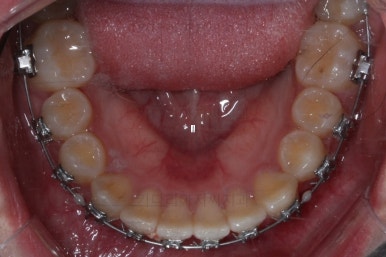

마무리 때의 모습입니다.

임시 개념으로 치아 사이즈를 키운건데 환자분은 만족하시나봐요.

보통 올세라믹, 라미네이트 등 보철치료는 성인이 되어서 해야해서 이래나 저래나 이정도에서 만족하기로 했습니다.

치아는 매우 가지런해졌고 뾰족하던 앞니의 형태도 좋아졌어요.

매복되어 있던 송곳니도 잘 나왔고 과개교합도 물론 개선이 되었습니다.